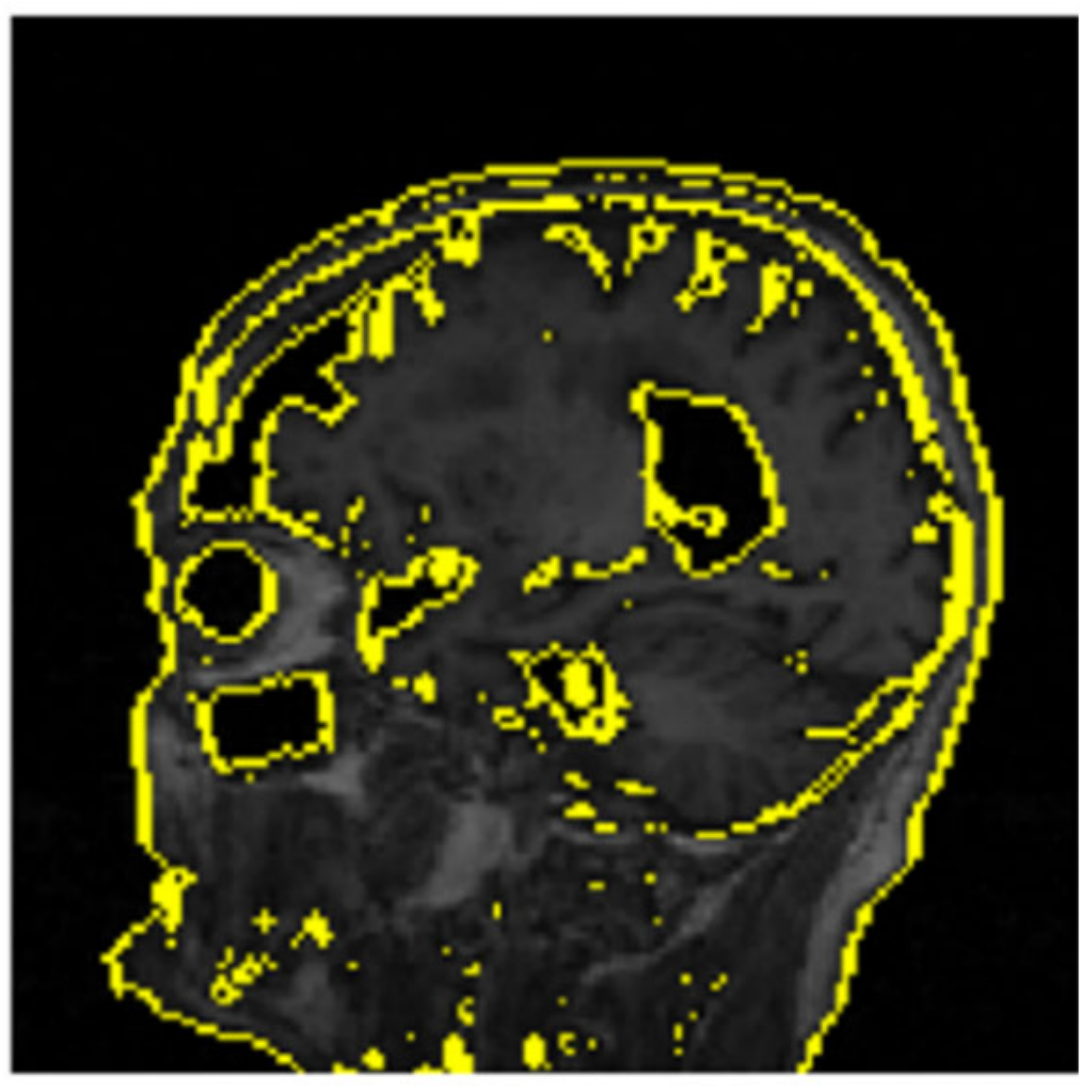

Given that the LIME methodology includes perturbing the instance x , sampling perturbed instances z from the neighborhood, obtaining predictions from the black box model f , and fitting an interpretable model g to locally approximate f s behavior, the interpretable representation X is utilized to emphasize significant features or regions represented by superpixels. The deactivation of these pixels returns a greyed-out representation of excluded features in the model’s prediction (Figure 6). Conversely, the activation of superpixels returns a mapping of feature regions that were relevant to the model’s prediction (Figure 7).

The LIME Explainable Artificial Intelligence (XAI) model developed superpixels that highlighted the cortical atrophy of the gyri and the expansion of the sulci and ventricles resulting from cellular degeneration in its positive prediction for MCI. The Grad-CAM Explainable Artificial Intelligence (XAI) model generated a heat map that revealed the highest activity concentration in regions near the parahippocampal gyrus, corresponding to the distinctive pathological features of Alzheimer’s disease (AD). In the early stages of AD, this region has a significant neuronal loss, characterized as mild cognitive impairment. These explainable artificial intelligence (XAI) solutions can effectively bridge the trust gap and enable medical practitioners from other fields to confidently make accurate assessments, utilizing AI as a transparent and supportive tool.

Figure 6. Perturbed instances from the predicted image in Figure 5 showing deactivated pixels.

Figure 7. Activated pixels displaying relevant features for the positive MCI prediction.